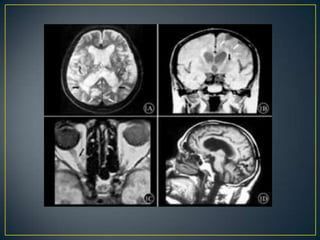

La esclerosis múltiple(EM) es una enfermedad consistente en la aparición de lesiones desmielinizantes, neurodegenerativas y crónicas del sistema nervioso central. Actualmente se desconocen las causas que la producen aunque se sabe a ciencia cierta que hay diversos mecanismos autoinmunes involucrados.

• Se caracterizapor dos fenómenos: • Aparición de focos de desmielinización esparcidos en el cerebro y parcialmente también en la médula espinal causados por el ataque del sistema inmunitario contra la vaina de mielina de los nervios. • Las neuronas, y en especial sus axones se ven dañados por diversos mecanismos